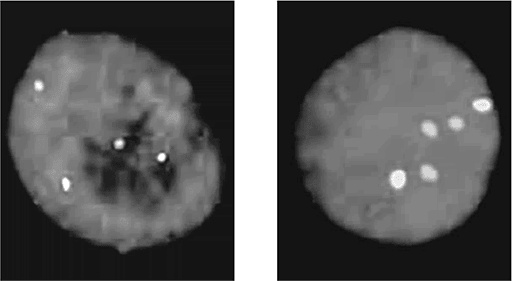

Иллюстрация к книге — ДНК. История генетической революции [i_153.jpg]

Флуоресцентное окрашивание, позволяющее определить число хромосом. Ядро клетки (синее) анализируется на присутствие 10-й хромосомы (голубая) и 21-й хромосомы (розовая). Слева показан нормальный кариотип, в котором по два экземпляра обеих этих хромосом; справа – кариотип, соответствующий синдрому Дауна (три 21-х хромосомы)